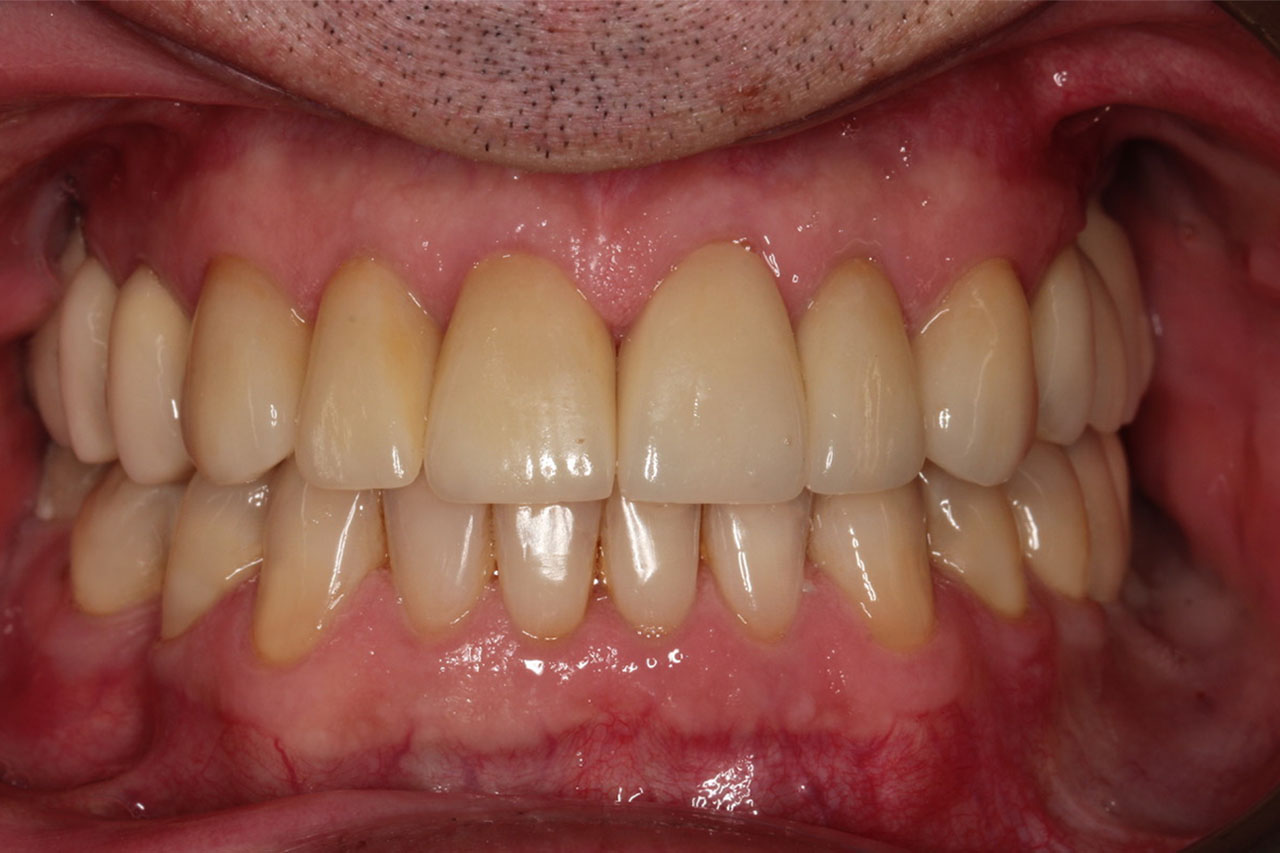

2. Licówki z indywidualną charakteryzacją (naturalnie wyglądające osady),

korony na implantach